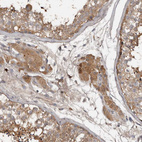

Anti-DNAJB4 Antibody

Polyclonal Antibody against HUMAN DNAJB4